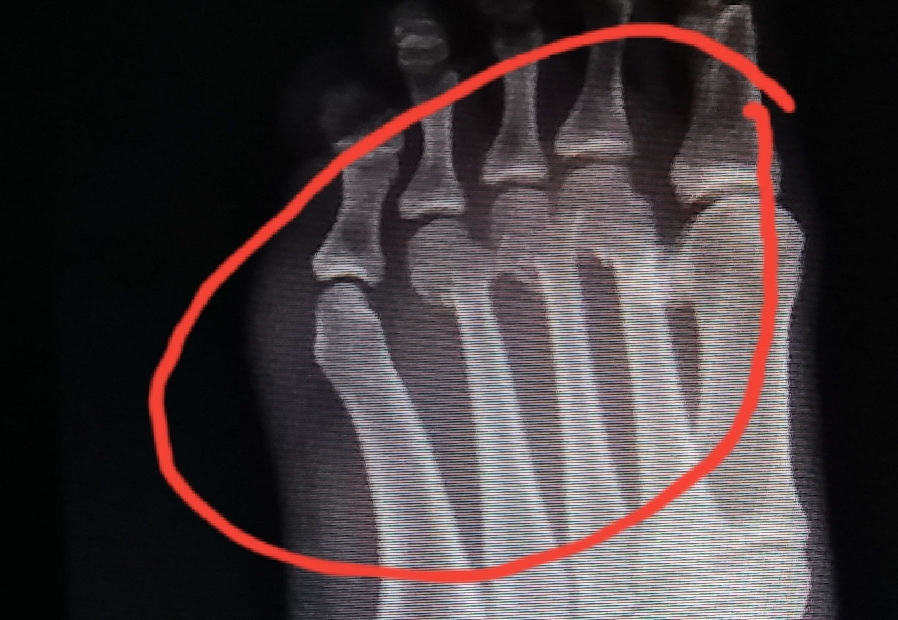

กระดูกส่วนปลายเท้าหักค่ะ คุณหมอเอาฟิลม์ให้ดูแล้วยัง งงๆ อยู่น่ะค่ะ รบกวนพี่ๆ ช่วยดูทีค่ะว่าแบบนี้ หักเยอะไหม